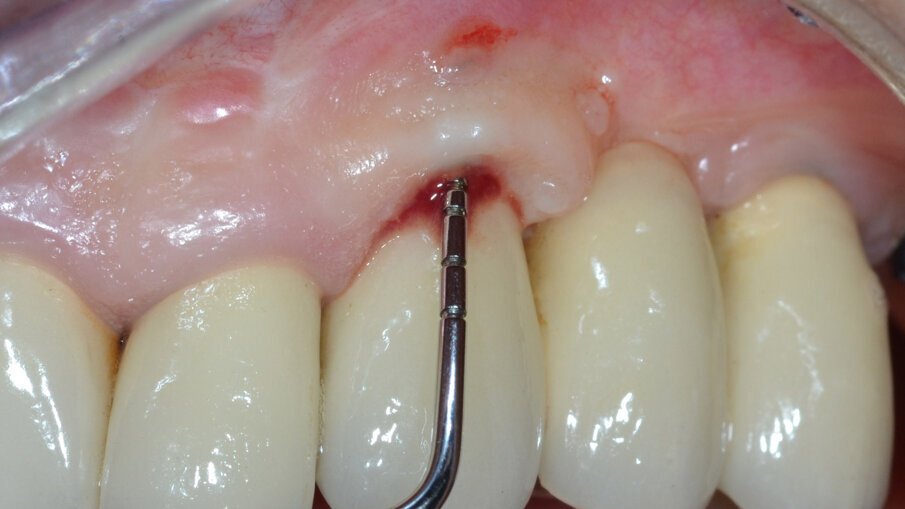

Paziente di aa 55, femmina, viene riferita per una sospetta peri-implantite in corrispondenza dell’impianto osteointegrato in zona 2.3; all’esame rx endorale e al sondaggio peri-implantare si evidenzia un riassorbimento osseo che interessa prevalentemente l’aspetto buccale: viene pertanto confermata la diagnosi di peri-implantite (Figg. 1, 2). Poiché l’esame radiografico endorale, a causa della sua natura bidimensionale, non sempre restituisce la reale morfologia del difetto osseo peri-implantare, è consigliabile incrociare i dati clinici, i valori del sondaggio e le immagini radiografiche raccolte al fine di evitare possibili errori diagnostici. Al momento della rivalutazione, sia lo stato dei tessuti molli peri-implantari che il livello di controllo di placca sono giudicati soddisfacenti e si programma un intervento di decontaminazione implantare associato a terapia rigenerativa del difetto intraosseo (G.B.R.) per mezzo di una membrana barriera di tipo riassorbibile sostenuta da un innesto osseo.

Fig. 1 - Sondaggio peri-implantare.

Fig. 2 - Esame RX endorale e sondaggio parodontale preperatorio.